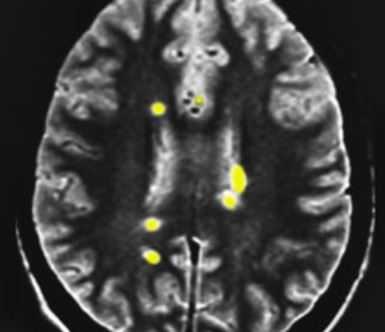

МРТ головного мозга. Т2-взвешенная аксиальная МРТ. Рассеянный склероз. Цветовая обработка изображения.

Разными авторами предлагались критерии постановки диагноза. Все они основанный результатах МРТ головного мозга. Главным для постановки диагноза служит наличие нескольких (от 2 до 9) типично расположенных на МРТ очагов. Локализация очагов может быть любая, но типичная - нижняя треть мозолистого тела, перивентрикулярно (вокруг желудочков мозга), ствол, спинной мозг. Форма очагов округлая и овоидная, направленная радиально от желудочков на сагиттальных (боковых) МРТ (симптом “пальца” или Доусона), что отражает перивенулярный (вокруг вен) процесс. Существует много предложений по оценке активности процесса. К сожалению, все способы оценки активности очень недостоверны. Обычно края активных очагов нечёткие, отмечается слабое контрастирование. Чувствительность и специфичность МРТ на самых ранних стадиях составляет 70-80%. Однако через очень короткий срок течения заболевания точность МРТ уже приближается к 100%.

МРТ головного мозга. Рассеянный склероз. Аксиальная МРТ Т2-взвешенного типа. Перивентрикулярные очаги.